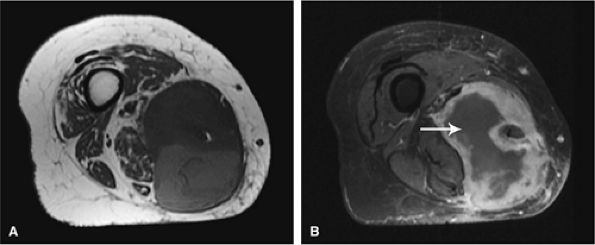

FIGURE 14-1 ● T1-weighted images (A) before and (B) after intravenous gadolinium administration show malignant fibrous histiocytoma. The tumor enhances after intravenous injection of gadolinium. Central tumor necrosis remains unenhanced (arrow).

Gadolinium has been used to enhance contrast on T1-weighted images to better characterize osseous and soft-tissue tumor involvement.2,7,15,22,23,24 On gadolinium-enhanced images, nonenhancing regions are thought to represent areas of nonviable tumor or necrosis (Fig. 14-1). Gadolinium-enhanced images may also be useful for differentiating peritumoral edema from underlying tumor and recurrent tumor from scar or fibrosis.25